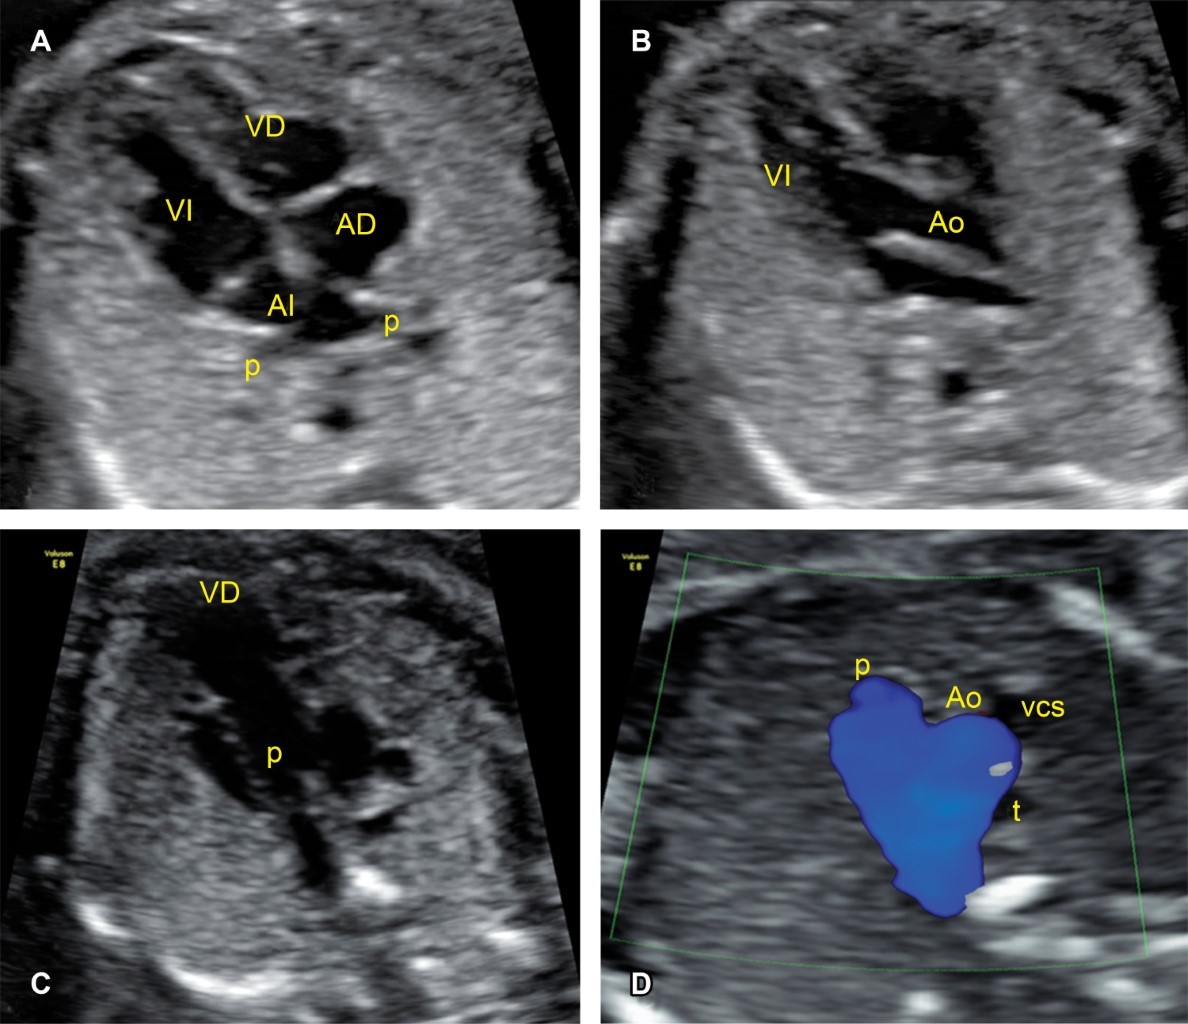

Figure 1